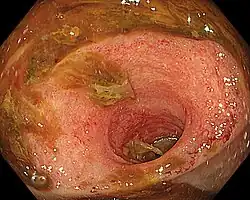

Ileitis caused by capecitabine.